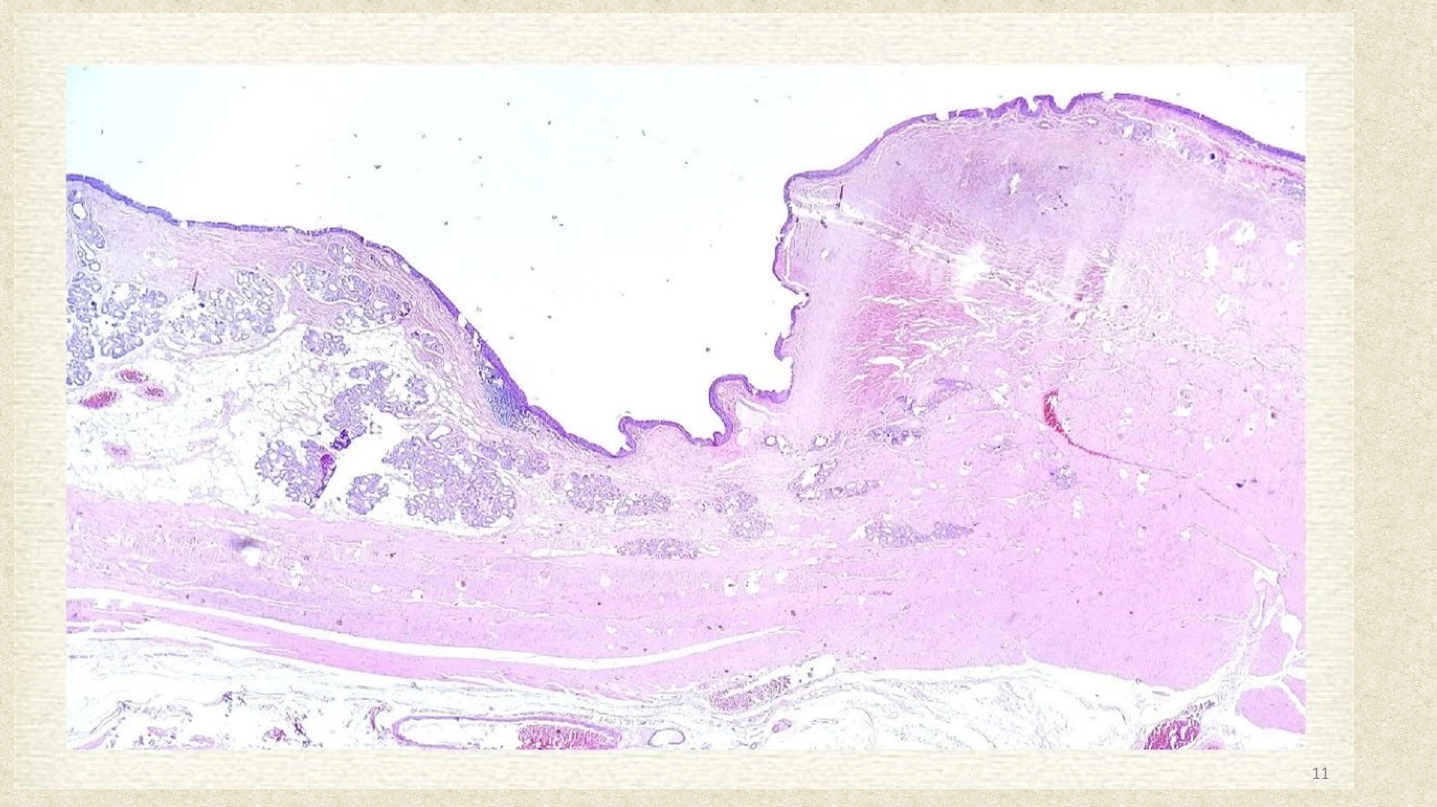

呼吸系统由呼吸道和肺构成。呼吸道包括鼻、咽、喉、气管及支气管,以环状软骨为界将其分为上、下两部分。

气管、支气管及细支气管均被覆假复层或单层纤毛柱状上皮或柱状上皮,肺泡表面覆盖两种肺泡上皮细胞。